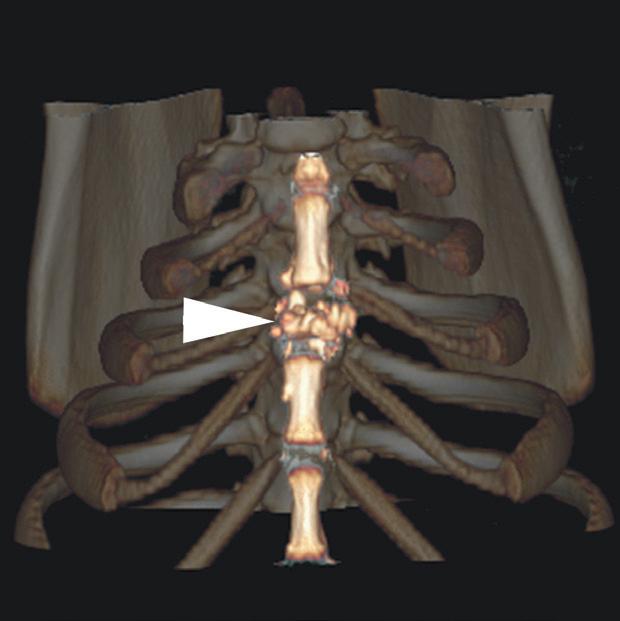

Rycina 4.1.5. Osteomyelitis mostka (pies) TK

Badanie wykonano u 18-miesięcznego, kastrowanego samca dobermana. Ryciny a i b przedstawiają kolejne obrazy poprzeczne doczaszkowej części klatki piersiowej w orientacji doczaszkowo-doogonowej. Widoczne jest nieuorganizowane niszczenie kości obejmujące drugi segment mostka (a–d – grot strzałki). Obecne jest również złamanie patologiczne (c – grot strzałki). Obustronnie widać umiarkowaną ilość płynu w jamie opłucnej w zgodnej grawitacyjnie przestrzeni opłucnowej (a, b – gwiazdki). Biopsja kości potwierdziła przewlekłe neutrofilowe zapalenie kości i szpiku, a cytologia płynu opłucnowego wykazała obecność zapalenia ropnego